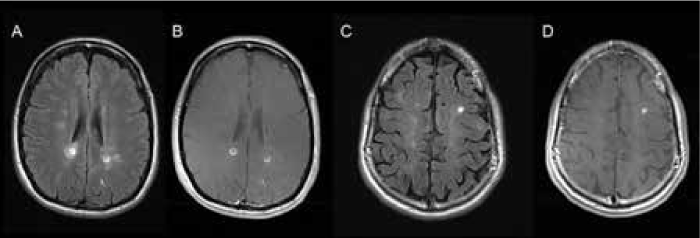

The qualitative approach demonstrated mixed results. On the one hand, the detection rate of ultrabright lesions was independent of the MRI magnet strength; on the other hand, the interrater agreement was moderate. Although the lesions of outstanding FLAIR hyperintensity (Figure 3) were unanimously categorized as ultrabright by both neuroradiologists, a proportion of lesions of above-average signal intensity are in the “grey zone,” which causes the neuroradiologists' disagreement. This, in our opinion, reflects the subjective nature of visual identification of ultrabright lesions.

Examples of “ultrabright” lesions